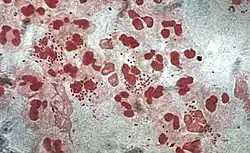

| Gonococcal lesion on the skin | |